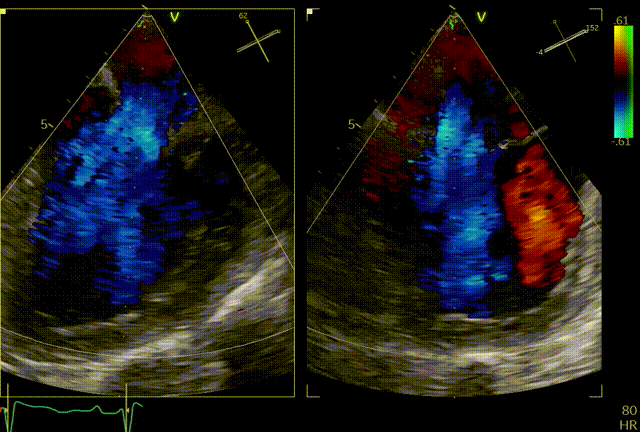

术前超声评估

二尖瓣前叶长度25.6mm,后叶长度12mm,对合深度约10.3mm,对合高度约为2mm,有效瓣口面积 5.5cm²。诊断二尖瓣重度关闭不全,考虑FMR。

术前TEE显示重度功能性二尖瓣反流,反流位于A2/P2

术后超声评估

术后TEE显示二尖瓣双孔化形成,瓣膜夹稳定